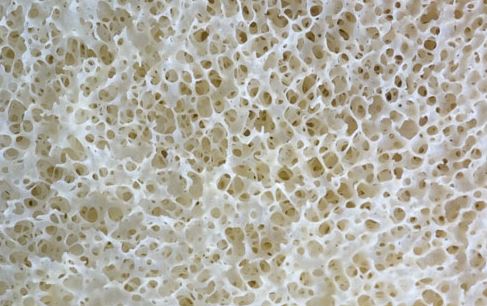

Βιταμίνη D: Για υγιεί οστά

Η βιταμίνη D είναι ζωτικής σημασίας για ισχυρά οστά. Βοηθά το σώμα να απορροφά το ασβέστιο από τα τρόφιμα. Σε ηλικιωμένους ενήλικες, η ημερήσια δόση βιταμίνης D και ασβεστίου βοηθούν στην πρόληψη των καταγμάτων και των εύθραυστων οστών. Τα παιδιά από την άλλη χρειάζονται τη βιταμίνη D για να χτίσουν ισχυρά οστά και να αποτρέψουν την ραχίτιδα.

Οι περισσότεροι άνθρωποι με χαμηλά επίπεδα βιταμίνης D δεν παρατηρούν συμπτώματα. Μια σοβαρή ανεπάρκεια στους ενήλικες μπορεί να προκαλέσει μαλακά οστά, μια κατάσταση που ονομάζεται οστεομαλακία. Τα συμπτώματα περιλαμβάνουν πόνο των οστών και μυϊκή αδυναμία. Στα παιδιά, μια σοβαρή ανεπάρκεια μπορεί να οδηγήσει σε ραχίτιδα και συμπτώματα μαλακών οστών και σκελετικών προβλημάτων.